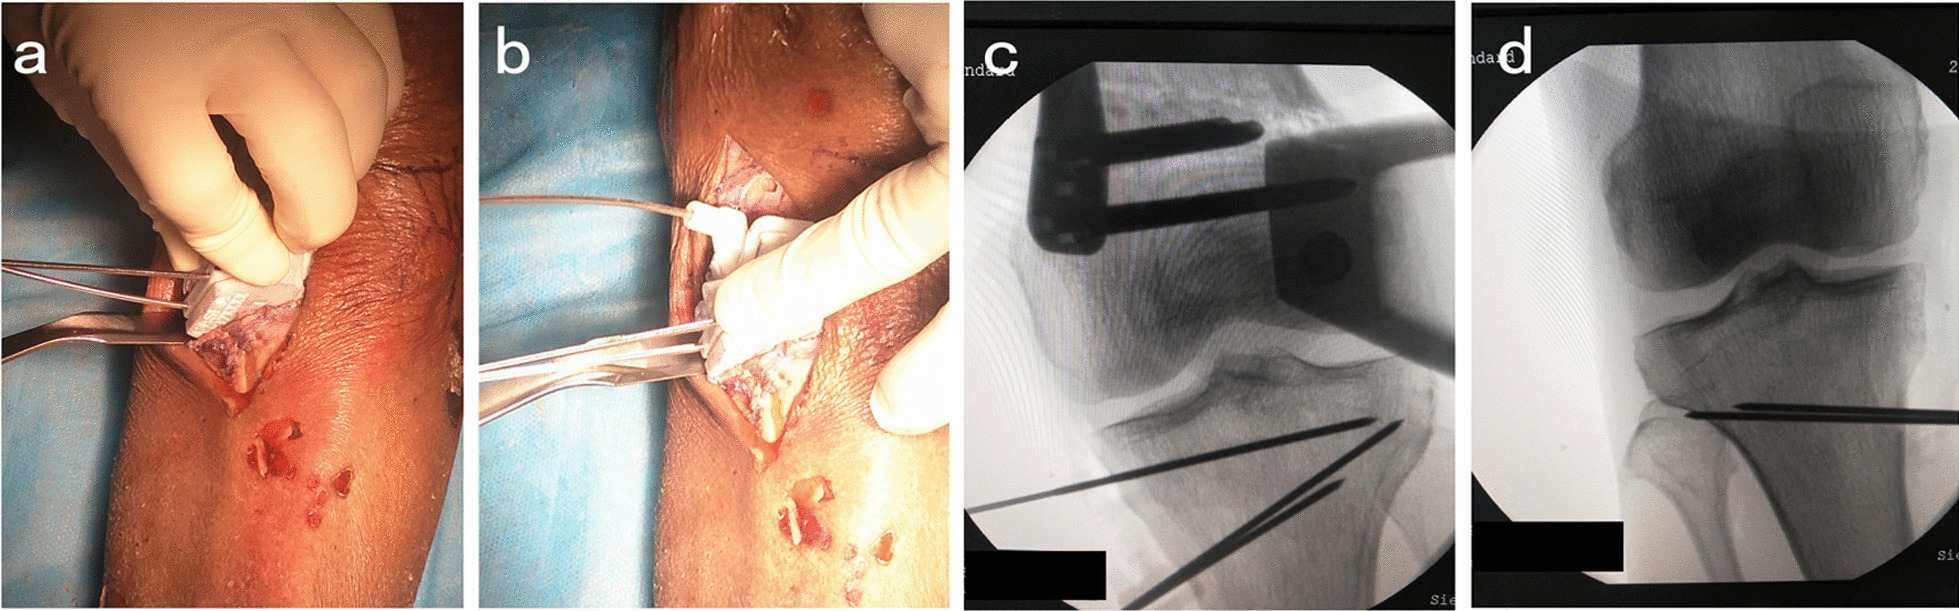

Fig. 3.

Insertion of K-wires. The K-wire was inserted through K-wire fixation sleeves (No. 1, No. 2, No. 3) (a, b). The K-wire (No.1, No.2) was inset at 3–4 cm below the medial tibial plateau. The position of the lateral hinge was suggested to be about 5–10 mm from the lateral edge of the tibia plateau. The K-wire (No.1, No.2) direction is the line between the uppermost end of the fibular head and the medial cutting point and the sawing depth should be reserved for 1 cm width of the lateral hinge (c, d)